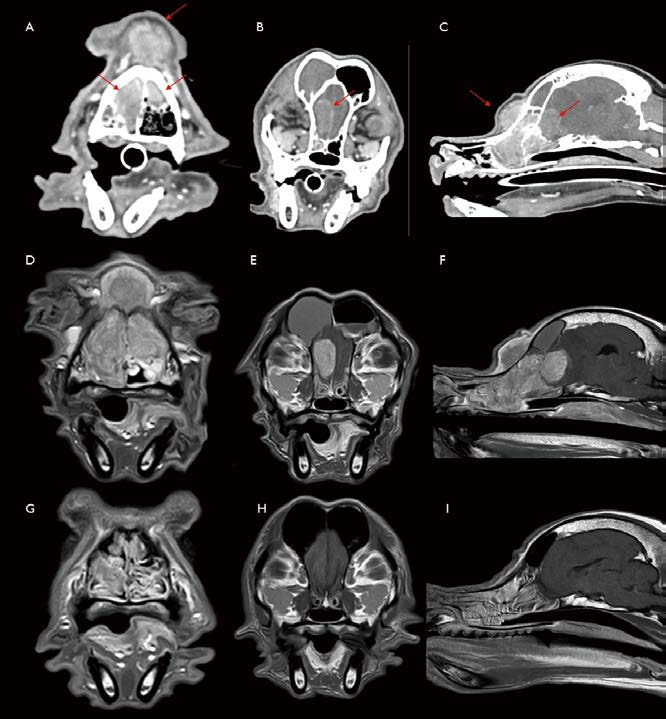

[대한수의사회지 7.png

8살 중성화 암컷 Miniature Schnauzer가 6개월 전부터 재채기, nasal discharge 증상을 보였고, 최근 왼쪽 편측으로 비출혈이 동반되었습니다. Plain X-ray에서 왼쪽 비강 내 밀도 증가 소견이 관찰됩니다(그림 7. A). CT 검사에서 왼쪽 비강 전반적으로 연조직 밀도 음영으로 채워져 있고, 일부는 nasal turbinate가 소실되어 관찰됩니다(그림 7. B, C). Nasal septum 및 large bones의 destruction은 관찰되지 않습니다. 영상학적으로 편측성이며, 일부는 nasal small bone loss를 유발한 space occupying mass 양상이므로 종양 가능성을 염두에 두고 rhinoscopy 및 여러 군데 biopsy를 실시했는데, 조직 검사는 lymphoplasmacytic to suppurative rhinitis로 확인되었습니다. 환자는 내과적 관리를 받기로 했고, sneezing 및 간헐적인 비출혈 등의 증상이 wax and wane 상태를 지속하였습니다. 전신 상태는 양호하였습니다. 그러나 1년 5개월 뒤, 왼쪽 muzzle 부위 부종, 통증 증상으로 다시 내원하였습니다. Plain X-ray에서 양쪽 비강 내 밀도가 모두 증가되어 있었고(그림 7. D), CT 검사에서 특히 왼쪽 비강 내 보다 명확해진 이질적 종괴 음영 및 이로 인한 상악골 소실 및 좌측 안구 앞쪽으로 종괴의 bulging 소견이 관찰됩니다(그림 7. E, F). 환자는 Biopsy 조직 검사에서 nasal carcinoma로 진단되었습니다. Radiation therapy 2개월 후 Plain X-ray(그림 7 G), CT 검사(그림 7. H, I)에서 오른쪽 비강 병변은 대부분 개선되었고, 왼쪽 비강 바깥으로 돌출된 부위와 왼쪽 비강 내부 일부에서도 종괴의 크기는 감소하였습니다. 환자는 비강 종양 진단 이후 방사선 치료와 보존 요법을 병행하면서 약 3년 동안 생존하였습니다.